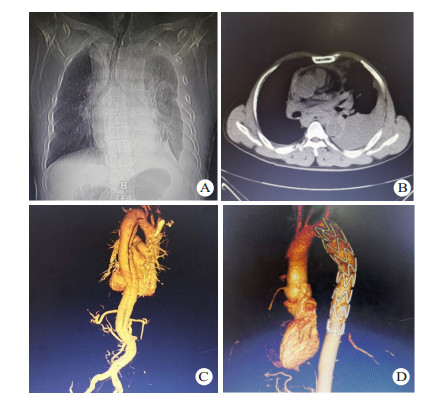

1 资料与方法 1.1 一般资料全组共14例,男性11例,女性3例,年龄23~71岁。急诊入院时间为伤后1~18 h。致伤因素包括车祸伤7例,高处坠落伤5例,重物砸伤1例,胸部击打伤1例; 车祸伤、高处坠落伤等钝性损伤患者不同程度伴有脑部受损,腹腔脏器破裂,血气胸或四肢、骨盆、肋骨、脊椎等骨折。其中伴血胸7例,肋骨骨折5例,四肢骨折3例,肝破裂1例,脾破裂1例,消化道穿孔1例,脑部受损1例,骨盆骨折1例,脊椎骨折1例。既往高血压病史5例。所有患者均由胸腹主动脉断层摄影血管造影(computed tomography angiography,CTA)明确诊断,均为Stanford B型主动脉夹层。夹层累及范围包括:胸主动脉夹层10例,胸腹主动脉夹层4例,肠系膜上动脉、肠系膜下动脉、左肾动脉受累各1例。本研究获得医学伦理委员会批准,编号:2018ER(A)037。治疗及检查均获得患者或家属知情同意。部分患者术前影像学资料见图 1。

| 图 1 患者男性,43岁,因车祸伤致胸背部疼痛入院,CTA诊断为TAD(A:普通胸片提示上纵隔明显增宽,隐约可见主动脉弓,左侧胸腔可见包裹性积液; B:胸部CT示降主动脉分层,可见真假腔,并可见左侧胸腔积液; C:胸腹部CTA提示自降主动脉起始部至前动脉起始部主动脉夹层,主动脉内径增宽; D:术后1年胸腹部CTA,支架位置良好,无移位,无内漏,无新发夹层或动脉瘤) |